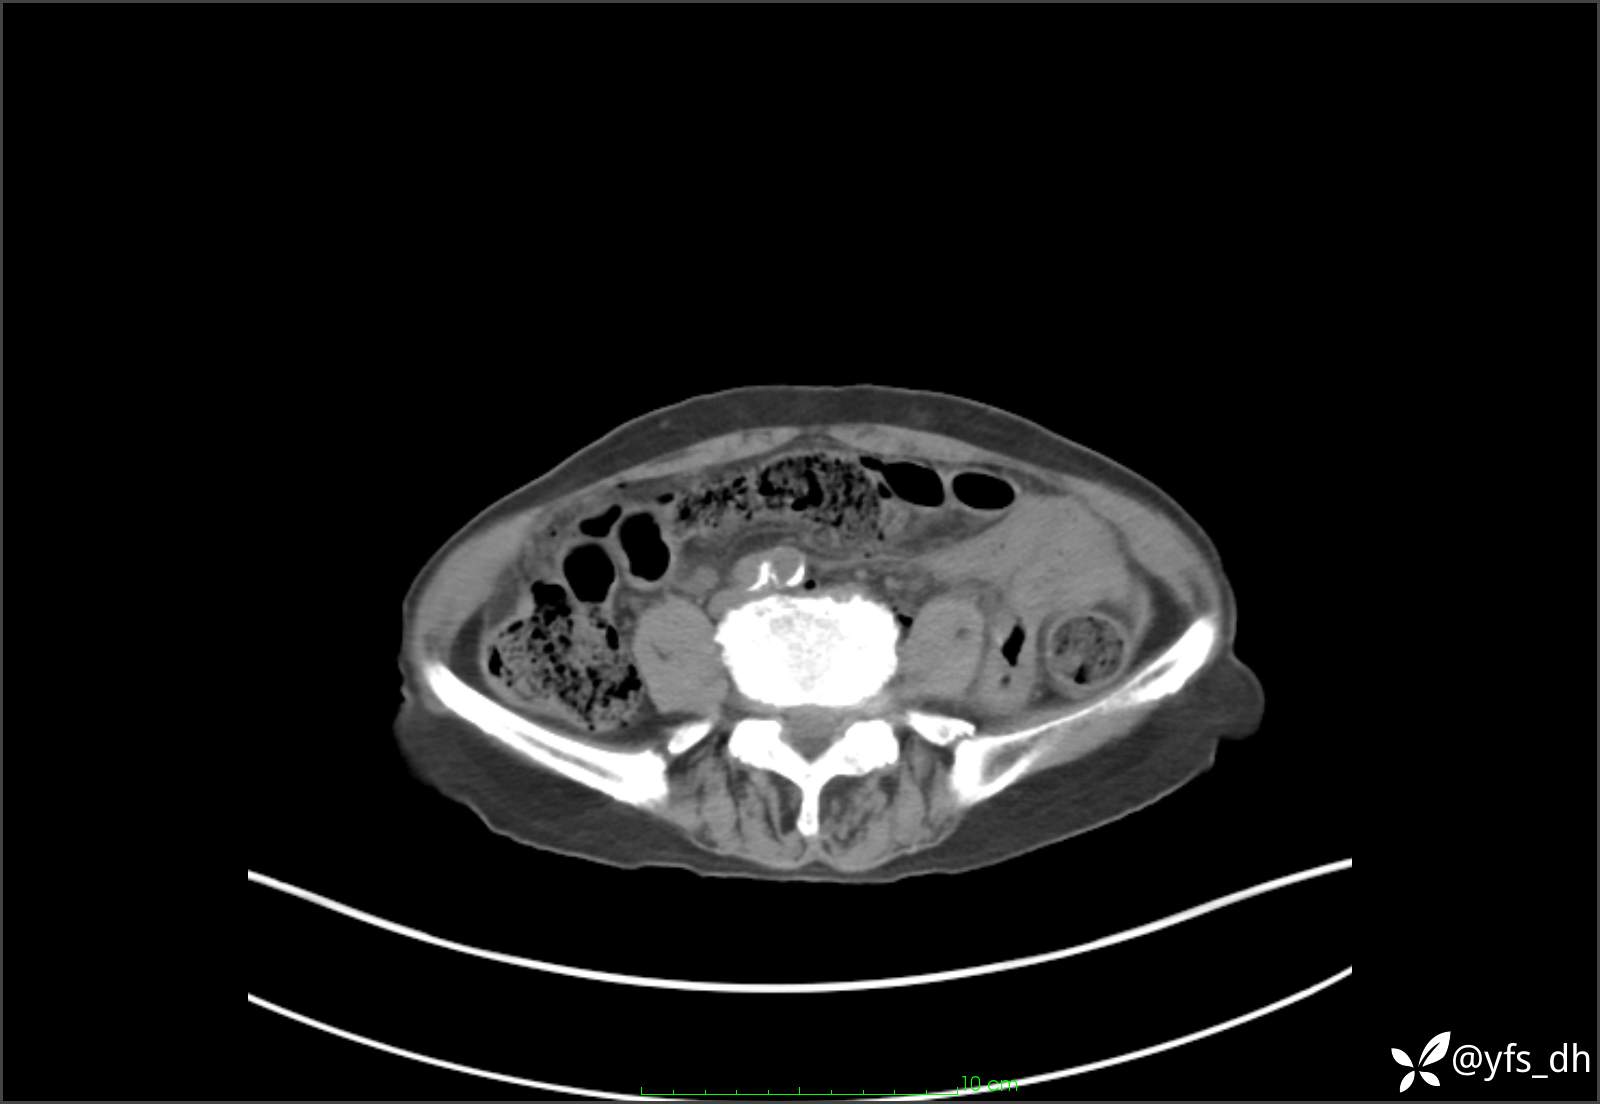

1.简要病史:患者4天前突发上腹部疼痛不适,但可以忍受。3小时前饭后突然加重,不能忍受后就诊。

2.简要手术记录:术中见腹盆腔大量肠液及粪便,乙状结肠中下段见一约3cm的破口。